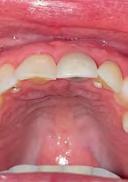

A healthy, 56-year-old female presented with fractured, endodontically treated tooth #9. The tooth was fractured at the gingival level and asymptomatic. Both the patient and the restorative dentist had high esthetic expectations, and preferred immediate implant placement with provisionalization if possible.

1. Pre-operative image showing a fractured, endodontically treated tooth #9.

1. Pre-operative assessment demonstrates minimal zone and thickness of buccal keratinized gingiva, with a medium periodontal phenotype.